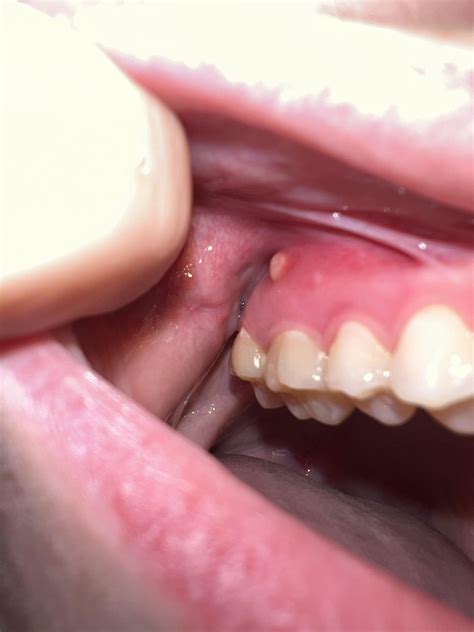

Gum boils, also known as periodontal abscesses or gum abscesses, are localized infections that occur in the gums. They are typically characterized by a small, pus-filled bump that can be quite painful. These boils can develop due to various reasons, including poor oral hygiene, trauma to the gums, or underlying dental issues.

- Pus Discharge: A small, pus-filled bump may be visible on the gum line.

To better understand what gum boils look like, it can be helpful to view pictures of gum boils. These visual aids can provide a clearer picture of the condition and help in identifying it. While it's important to note that pictures of gum boils can be graphic, they serve as valuable educational tools.